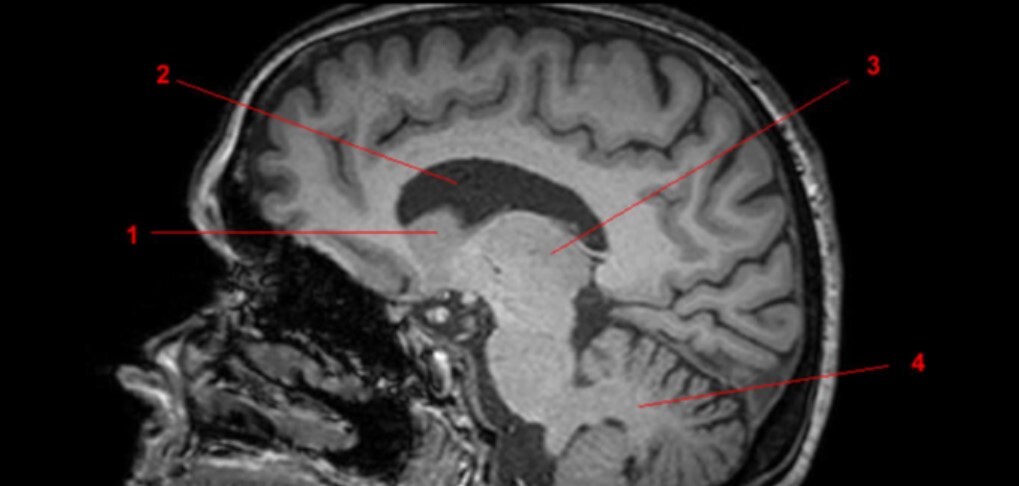

Label 1-9

1=Rostrum (CC)

2-Genu (CC)

3-Body (CC)

4=Splenium (CC)

5=Lateral ventricle

6=Thalamus

7=Midbrain

8=Pons

9-Medulla oblongata

Label 10-18

10-4th ventricle

11=Cerebellum

12=Cisterna Magna

13=Basilar artery

14=Clivus

15-Mamillary body

16=Optic chiasm

17=Infundibulum

18=Occipital bone

Label 19-27

19=Sphenoid sinus

20=Quadrigeminal cistern

21=Occipital lobe

22-Frontal lobe

23-Parietal lobe

25-Cerebral aqueduct

26-Frontal bone

27-Spinal canal